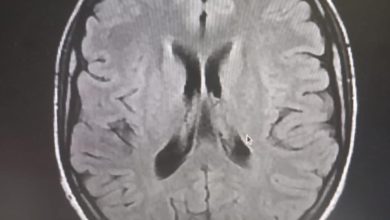

إجراء أول عملية ”تفتيت“ للجلطة الدماغية بالمستشفى العسكري في موريتانيا (صور)

(إحاطة)- أعلن الجيش الموريتاني أن فريقا طبيا بالمستشفى العسكري بنواكشوط تمكن من إجراء أول عملية تفتيت جلطة دماغية في موريتانيا.…